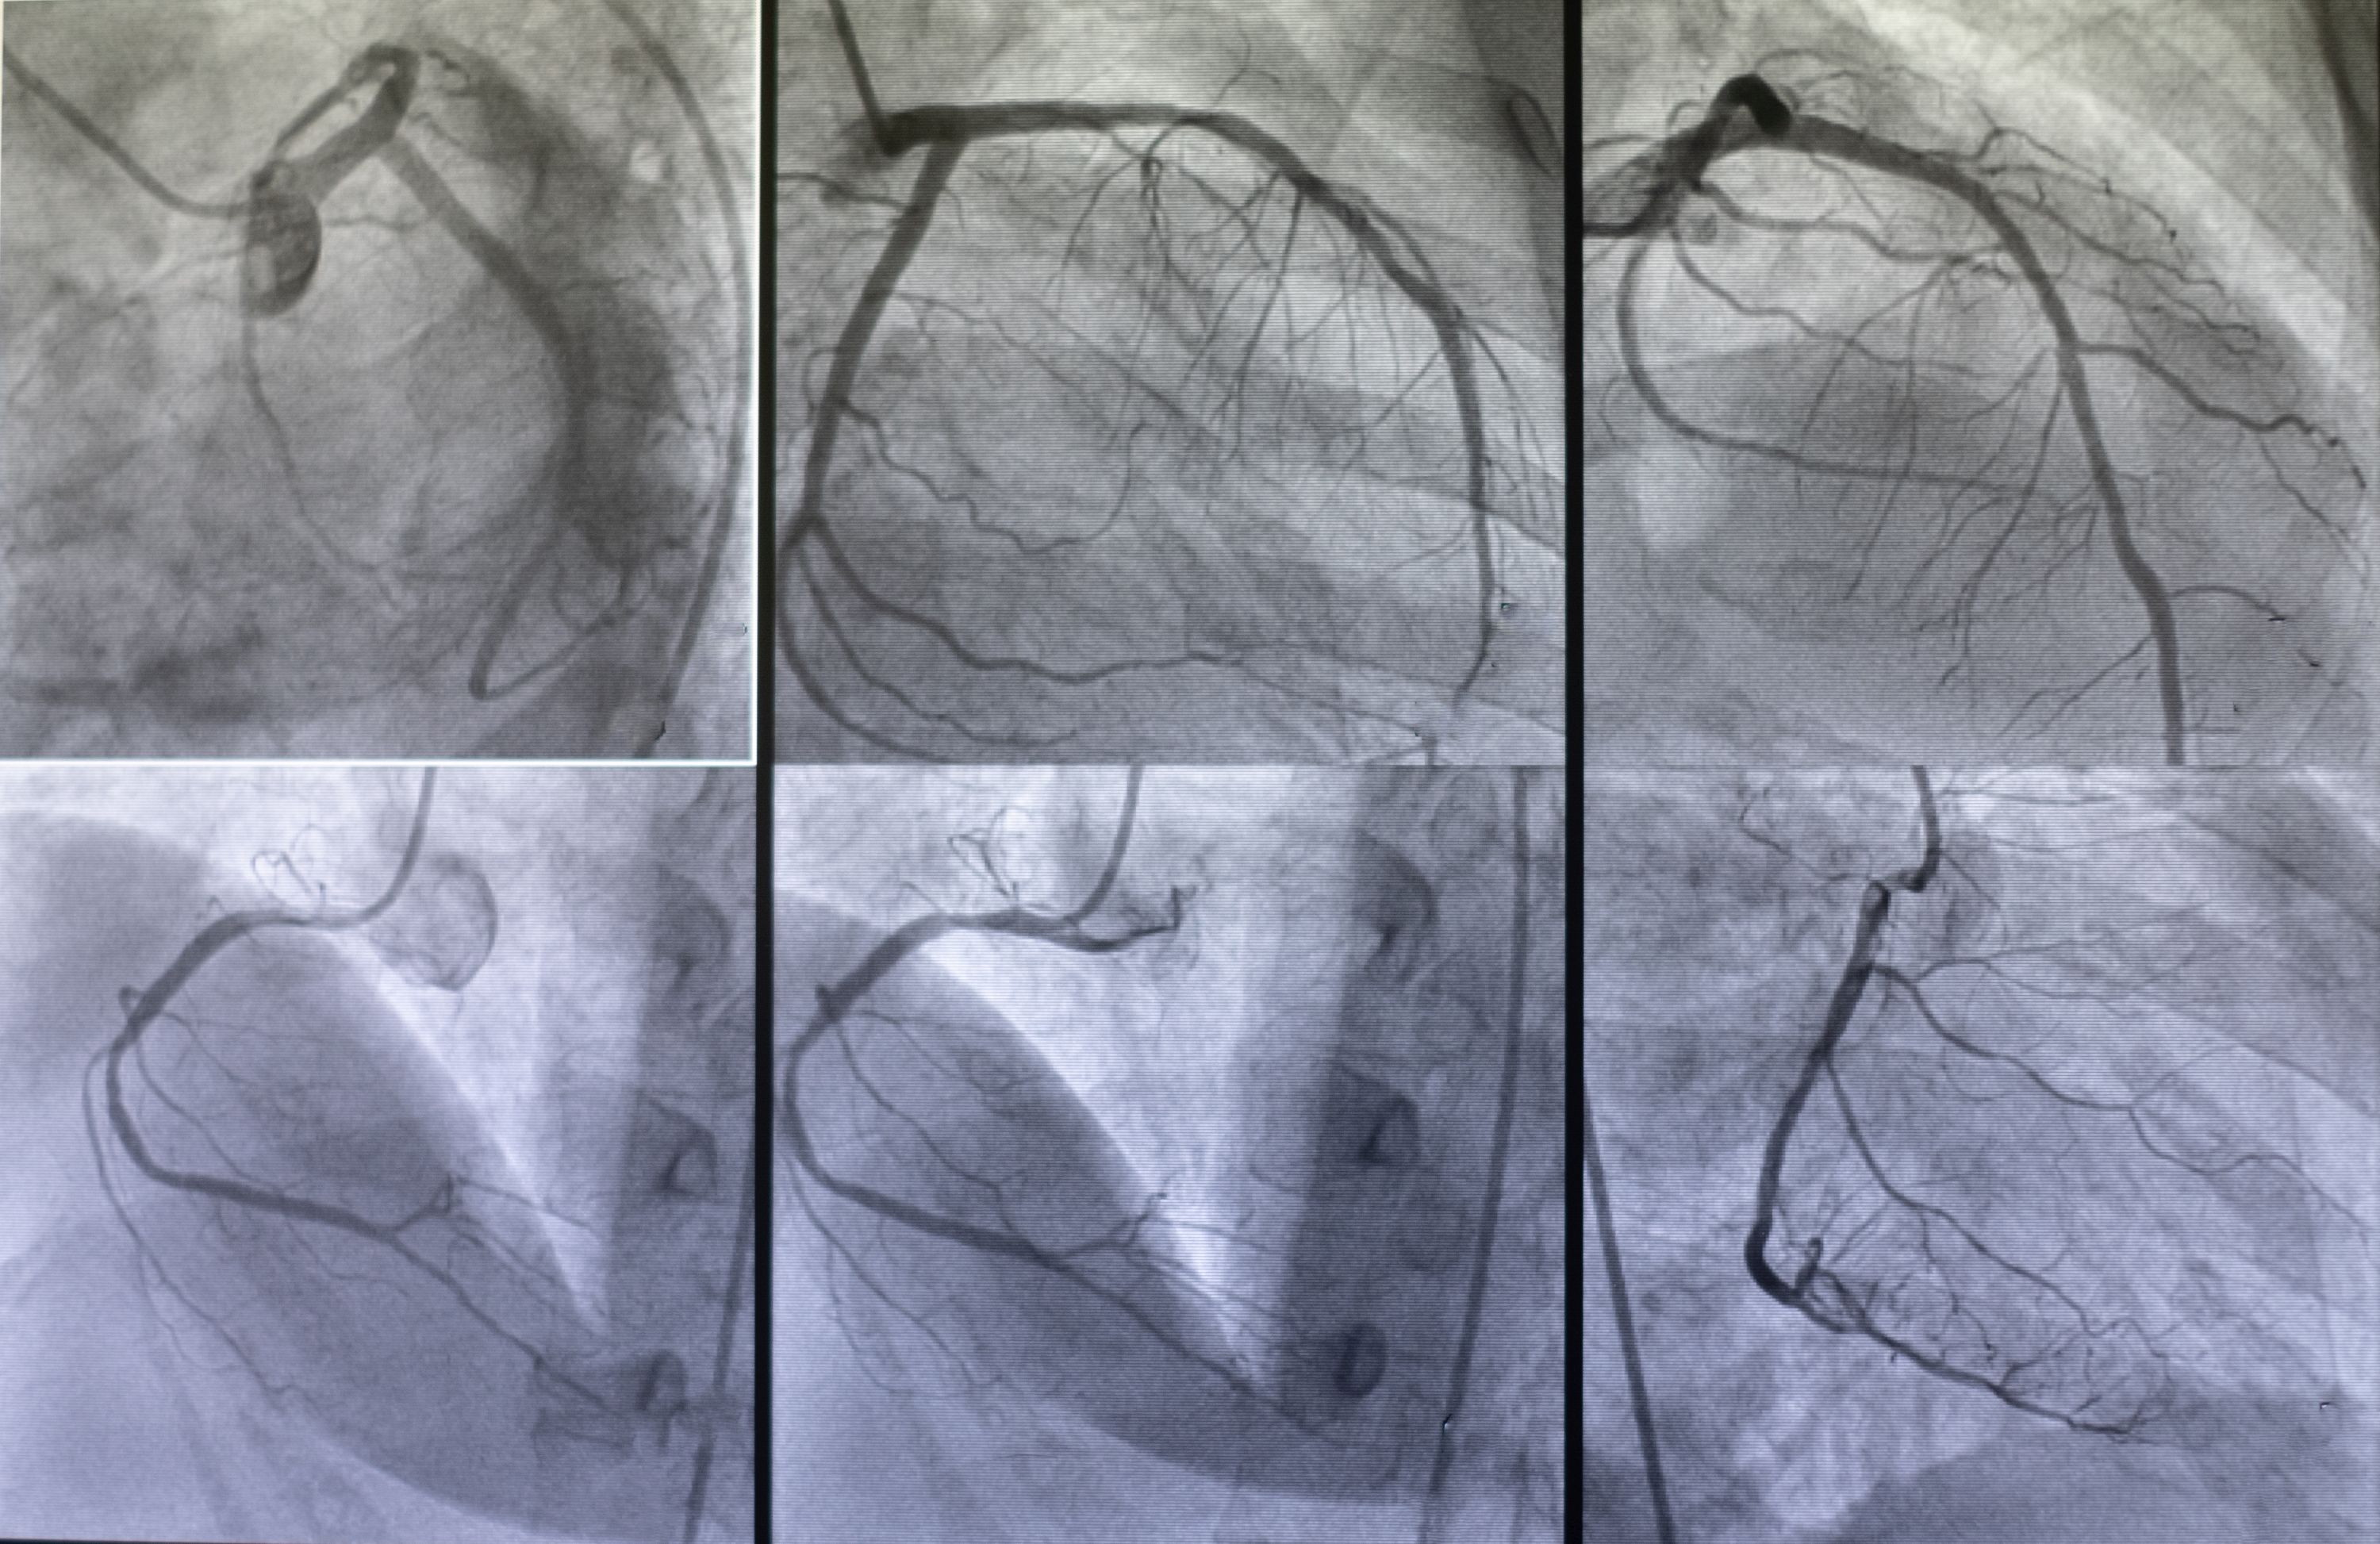

De arts plaatst een klein buisje in de slagader van de lies of de pols. Voorafgaand wordt de pols of lies lokaal verdoofd, zodat u dit niet voelt. Vervolgens worden via deze toegang katheters opgeschoven via de bloedvaten tot in de kransslagaders van het hart. Eens de katheter ter plaatse is in de kransslagader, worden video-opnames gemaakt van de kransslagaders, terwijl contraststoffen worden geïnjecteerd. De video’s worden gemaakt met een röntgenbuis, die tijdens het onderzoek boven uw lichaam in verschillende posities zal worden geplaatst. De manipulaties met de katheter in het lichaam wordt u niet gewaar. De injectie van contraststoffen in het hart kan wel leiden tot een warmtegevoel in het lichaam, plotse aandrang om te urineren of een lichte druk op de borstkas. Deze symptomen zijn kortdurend en verdwijnen spontaan.

Wanneer een vernauwing wordt gezien, is soms een aanvullende drukmeting in de kransslagader noodzakelijk, waarvoor specifieke medicatie wordt toegediend. De arts zal dit tijdens het onderzoek verder met u bespreken.

Indien er een ernstige vernauwing wordt vastgesteld, wordt aansluitend overgegaan tot behandeling met implantatie van een stent. Indien er meerdere vernauwingen of een complexe vernauwing worden vastgesteld, wordt de behandeling eerst verder besproken.